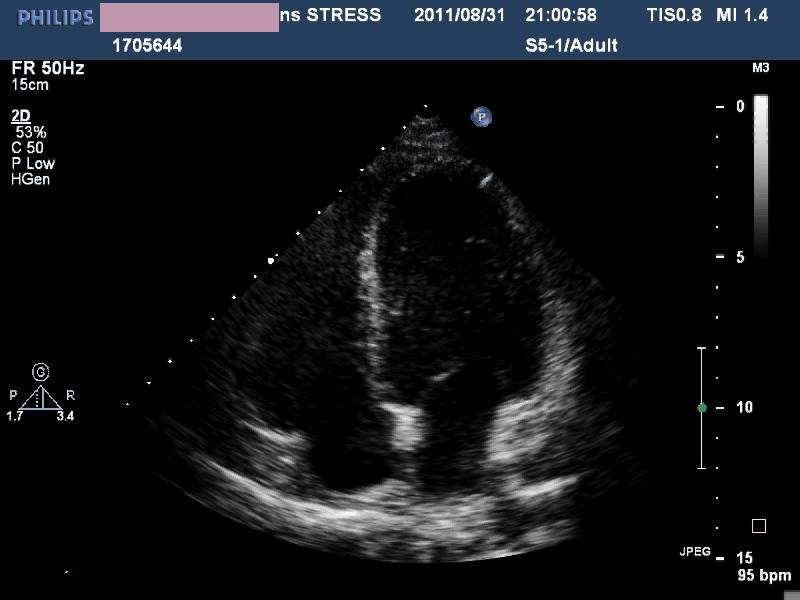

——各房室内径正常,左室收缩功能及室壁运动未见异常,LVEF 72%,少量心包积液(入院后1周)。

诊治经过-第二次心脏超声

◆感染之后出现

◆广泛心肌受累

◆初期有心肌坏死表现

◆心力衰竭

◆无心律失常

◆一周内完全恢复

——病毒性心肌炎?

应激性心肌病?

——根据随诊表现,患者最终诊为应激性心肌病